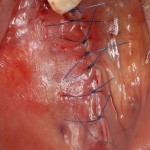

Остеопластика — всего одна операция.